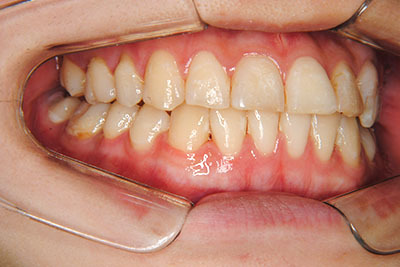

マルチブラケット装置(T21ブラケット)に加えて口の中のゴムをたいへん頑張って使っていただいた結果、治療前の予想期間1年から1年半であったところ、10カ月で動的治療を終了できました。上下真ん中のズレも治りぴったりになりました。 これからは歯並びの維持安定のためリテーナー(保定装置)を使いながら定期健診となります。

⑧リスクと副作用:マルチブラケット装置(T21ブラケット)を初めてつけてから3,4日、食事の時に歯が少し痛かったとのことでした。治療後のエックス線写真で、歯根吸収はほとんど観察されませんでしたが、歯肉を診ると残念ながら下の真ん中の前歯2本の間に若干の歯肉退縮(ブラックトライアングル)が生じていました。